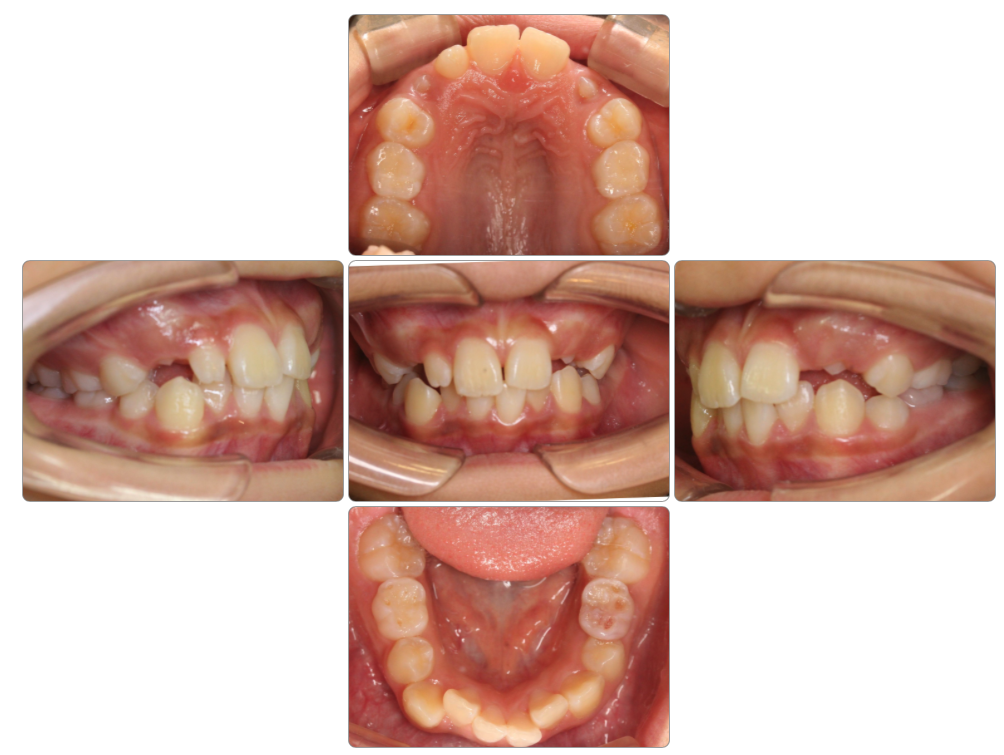

叢生の治療例

Before

after

| 初診時 | 9歳8ヵ月 |

| 治療期間 | 1年半 |

| 費用 | ¥550,000・調整料¥5,500/月 |

| 使用装置 | マイオブレイス |

| リスクと副作用 | |

| 原因と考察 | 頭位が上がった姿勢になっているために舌が口蓋(上顎)に触れていません。このため口蓋の広がりが悪く歯並びが小さくなっているようです。マイオブレイスと共に正しい姿勢で生活できるようになることでその後の後戻りリスクが下がると思います。 |